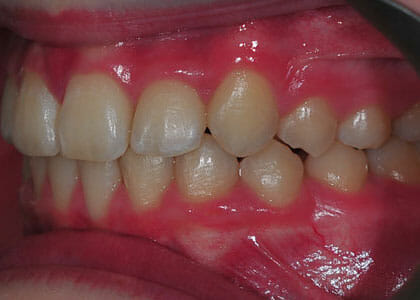

This lady hated her very uneven smile, all the teeth sticking out at the sides, teeth bunched together and uneven. We fitted clear brackets and a wire on the inside in the upper jaw in the roof of the mouth and in under 18 months the teeth were perfectly aligned and the patient’s smile was changed forever.